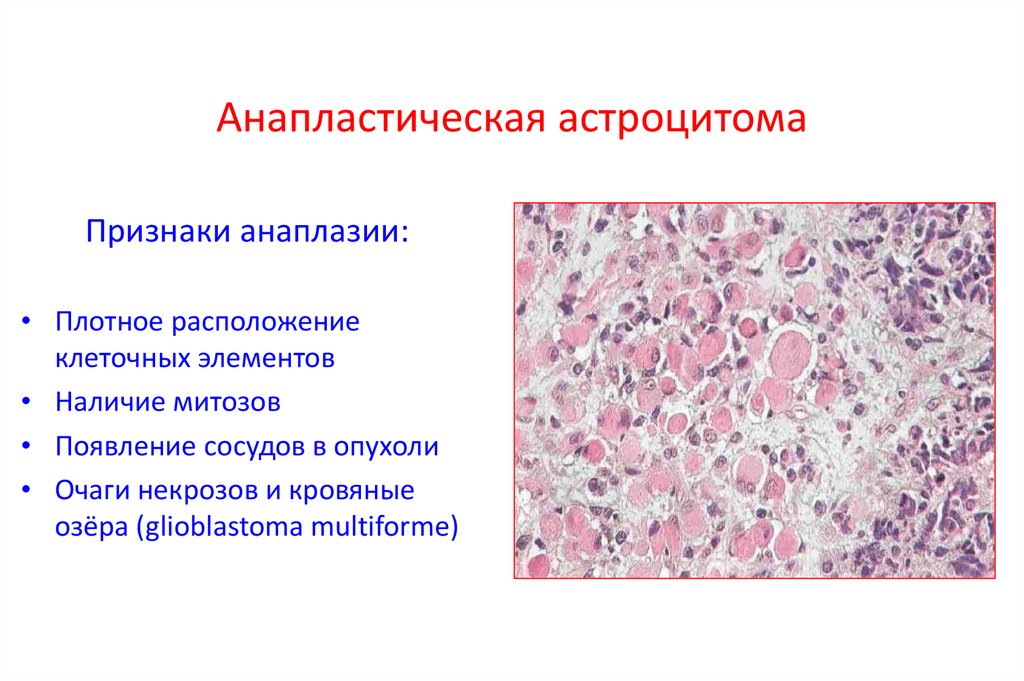

Микрофотографии гистологии глиобластомы головного мозга